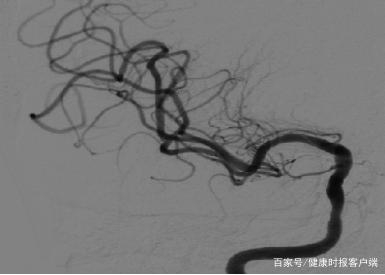

患者右侧颈内动脉C6段重度狭窄造影。受访者供图

“来院就诊的是一位80多岁高龄脑梗塞患者,手术前经过脑血管造影术检查显示,患者右侧颈内动脉C6段重度狭窄(狭窄程度75%),余颅内血管多发轻度狭窄,由于患者年龄较大,颈内动脉狭窄程度较重、狭窄位置高,所以医生与患者及家属反复沟通后,决定对患者进行颈内动脉支架成形术。”陈光利告诉健康时报记者。